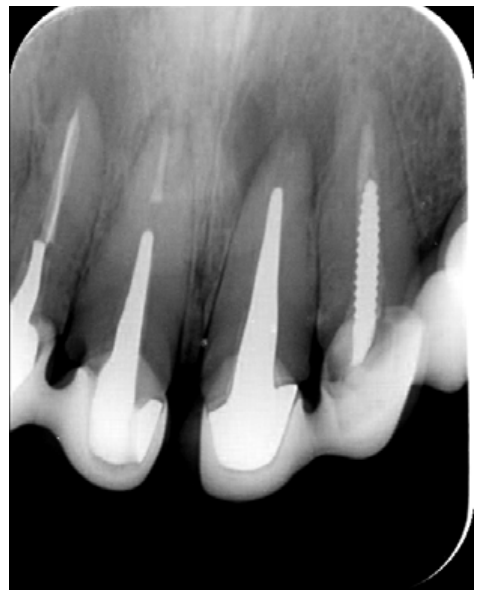

The patient provided an orthopantomography (OPG) as a radiological study (Figure 1). Periapical radiographs (Figures 2 and 3) were performed and a clinical examination including periodontal assessment of the affected teeth, without observing increased probing depths that could indicate the existence of endoperiodontal lesions.

To confirm the endodontic origin and the size of the lesions, tomographic examinations were performed with a slice thickness of 75 microns using CBCT CS8100 (Carestream Dental™), in which radiolucent periapical lesions were observed at the level of 12, 11, 21 (with bicortical involvement), 25 and vestibular roots at 26 (Figures 4 to 8).

Meanwhile, the vestibular roots of 26 showed clearly deficient root canal treatment, being underextended by several millimetres, as well as an omitted mesiopalatine canal (MP). Therefore, the need to repair the root canal treatment was proposed to the patient before performing microsurgery on tooth 25 (Figure 9).